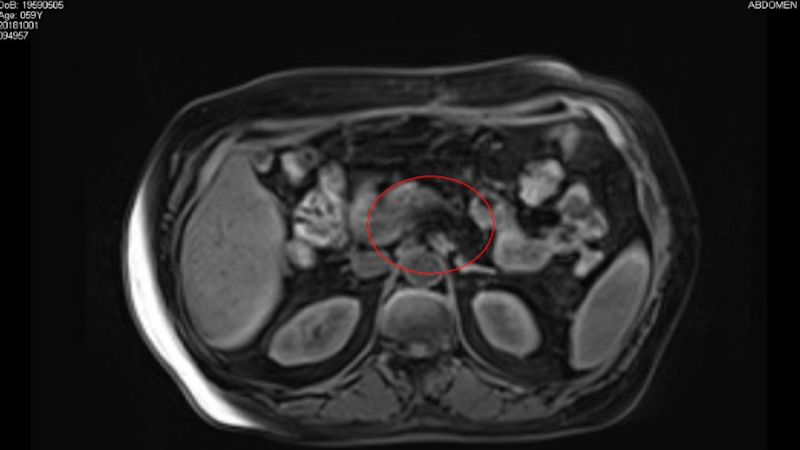

Слайд 21МРТ.

МРТ.

Слайд 38Клинический случай.

Инструментальные данные:

МРТ органов БП: в головке поджелудочной железы определяется

опухолевое образование размером 3,5х3,5 см. Опухоль сливается со стенкой подковы

двенадцатиперстной кишки, не исключено ее вовлечение. Опухолевый инфильтрат распространяется в чревно- брыжеечный промежуток, на одном из срезов имеется тесное прилежание опухоли к задней полуокружности ВБВ. ВБА представляется интактной.

Тело и хвост поджелудочной железы дистрофичны, панкреатический проток расширен до 0,5 см(норма: до 2 мм), «обрывается» на уровне опухоли.

В парапанкреатической клетчатке( на уровне опухоли) имеются л/у 0,5-0,9 см, сливающиеся с самой измененной головкой.

Клинический случай.Инструментальные данные:МРТ органов БП: в головке поджелудочной железы определяется опухолевое образование размером 3,5х3,5 см. Опухоль сливается